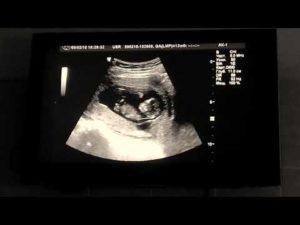

На видео, предоставленном каналом «Семья Воробей / Жизнь многодетной семьи», можно увидеть, как выглядит плод ребенка на 12-й неделе беременности.

На УЗИ в 12 недель движения малыша уже можно отследить. Его активность начиная с 7–8 недель беременности является важным показателем развития.

Фотогалерея

Снимок девочки, около 12 недель Снимок двойни Фото на УЗИ, девочка Фото на УЗИ, мальчик Снимок мальчика, 12 недель Разница в снимках УЗИ мальчика и девочки

В 12 недель беременности фото плода покажет вам, как вырос малыш. Это будет первым снимком ребенка.

Именно с этого периода начинаются самые интересные и удивительные перемены: малыш усиленно растет, функции всех его органов совершенствуются для того, чтобы потом после рождения быстрее акклиматизироваться к новым условиям обитания вне живота. В 12 недель беременности фото плода на УЗИ покажет вам ребенка, который значительно вырос с момента зачатия.